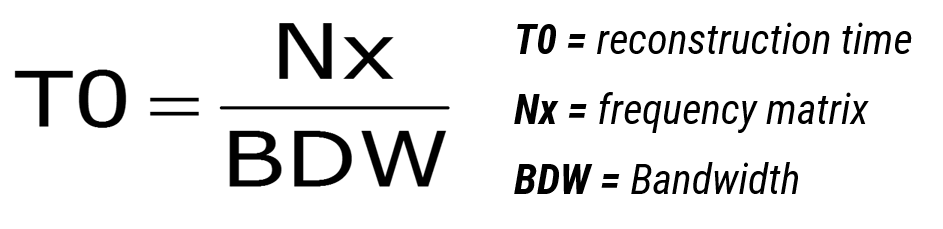

While reading the signal, a magnetic field gradient is applied. Thus, the received signal is composed of several signals, each having a particular frequency. The frequency matrix corresponds to the number of different frequencies that make up the signal. In fact the size of this matrix influences the reconstruction time. The higher the number of frequencies in a signal, the longer it will take for the system to view it.

Reconstruction Time

The inter-echo space depends on the reconstruction time. This is why the frequency matrix and the bandwidth have one impact on the inter-echo space. In fact, these parameters impact Max TE and the number of allowed slices per acquisition.

In this formula, the reconstruction time is equal to the frequency matrix divided by the matrix. As you can see both of these parameters have a direct impact on the time it takes to reconstruct an image.